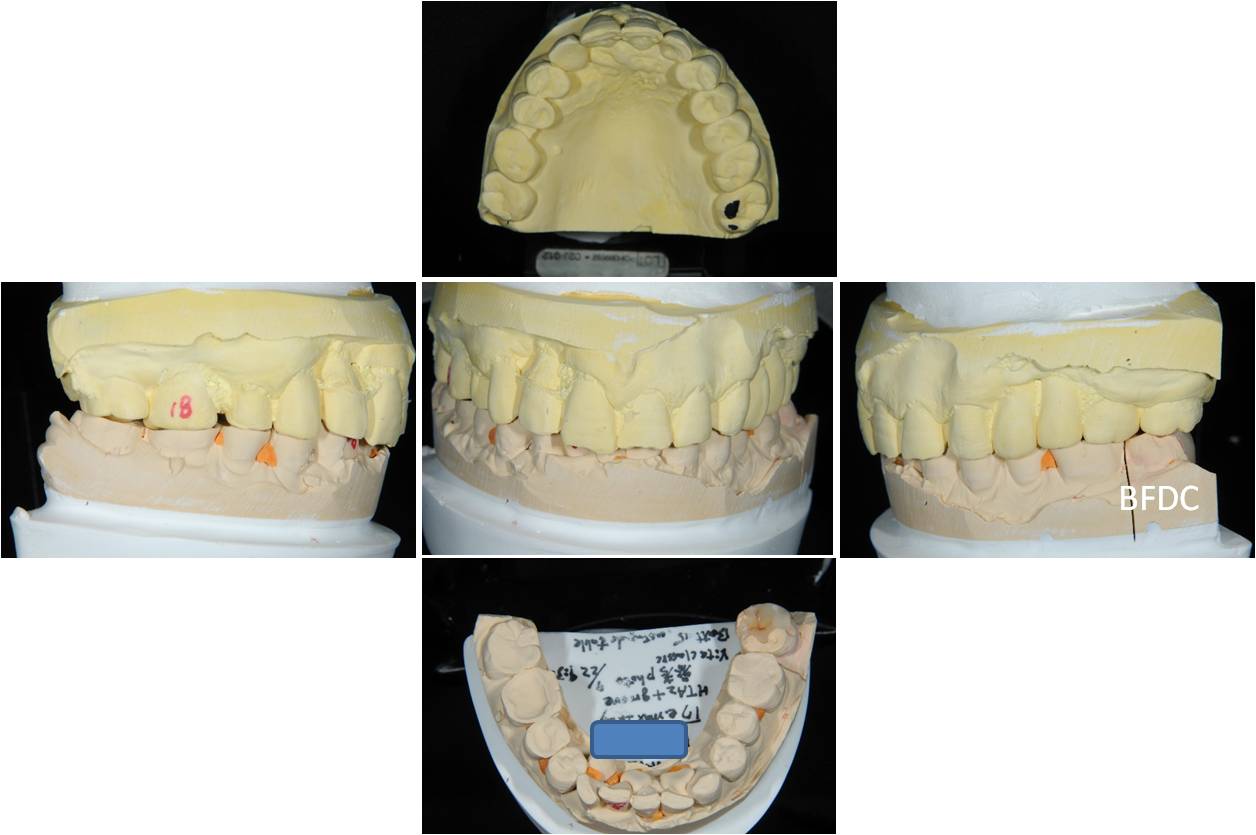

上咬合器

陶瓷冠蓋體製作